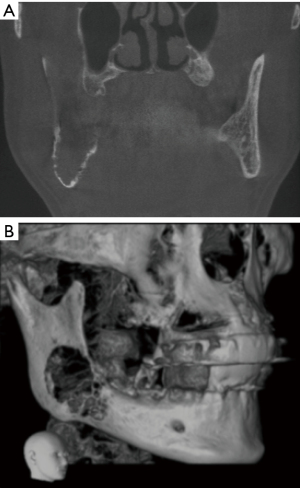

A physical examination revealed that the right side of the patient’s face was slightly swollen compared to the left side, and the mouth opening was normal. A bony prominence approximately 3.0 cm × 3.0 cm in size was palpable in the right mandibular angle area, accompanied by severe pain. The right mandibular second molar was loose at degree II, with no abnormality in the intraoral mucosa, and numbness in the right lower lip. A CBCT scan showed the bone in the right mandibular molar area to the mandibular angle was disorganized and resorbed severely, with unclear boundaries and rough edges. A small amount of needle-like periosteal bone formation was seen on the buccal and lingual sides, and the structure of the right mandibular neural tube in the lesion area was unclear (Figure 2).